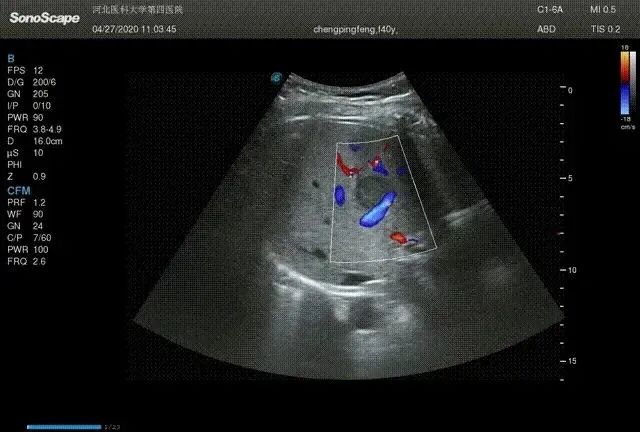

然而,2018年1月腹部CT发现肝脏多发转移。肝内可见多个低回声结节,边界清晰,周边可见低回声晕,大者位于右叶,另于肝右叶可见片状低回声,余肝实质回声致密,血管显示清晰,走行正常。

治疗2个月后,通过CT检查发现肝转移处于部分缓解状态。

之后PTX改为4周一次,一直到2018年11月PTX剂量进一步减至每4周一次65mg/m2。期间肝转移病灶也在进一步缩小,并且没有新的转移病灶出现。

一直到2022年5月,CT 扫描显示,肝转移保持缓解,患者已经稳定了 3 年,期间工作生活一切正常,而且没有新的病灶或肿瘤标志物升高。